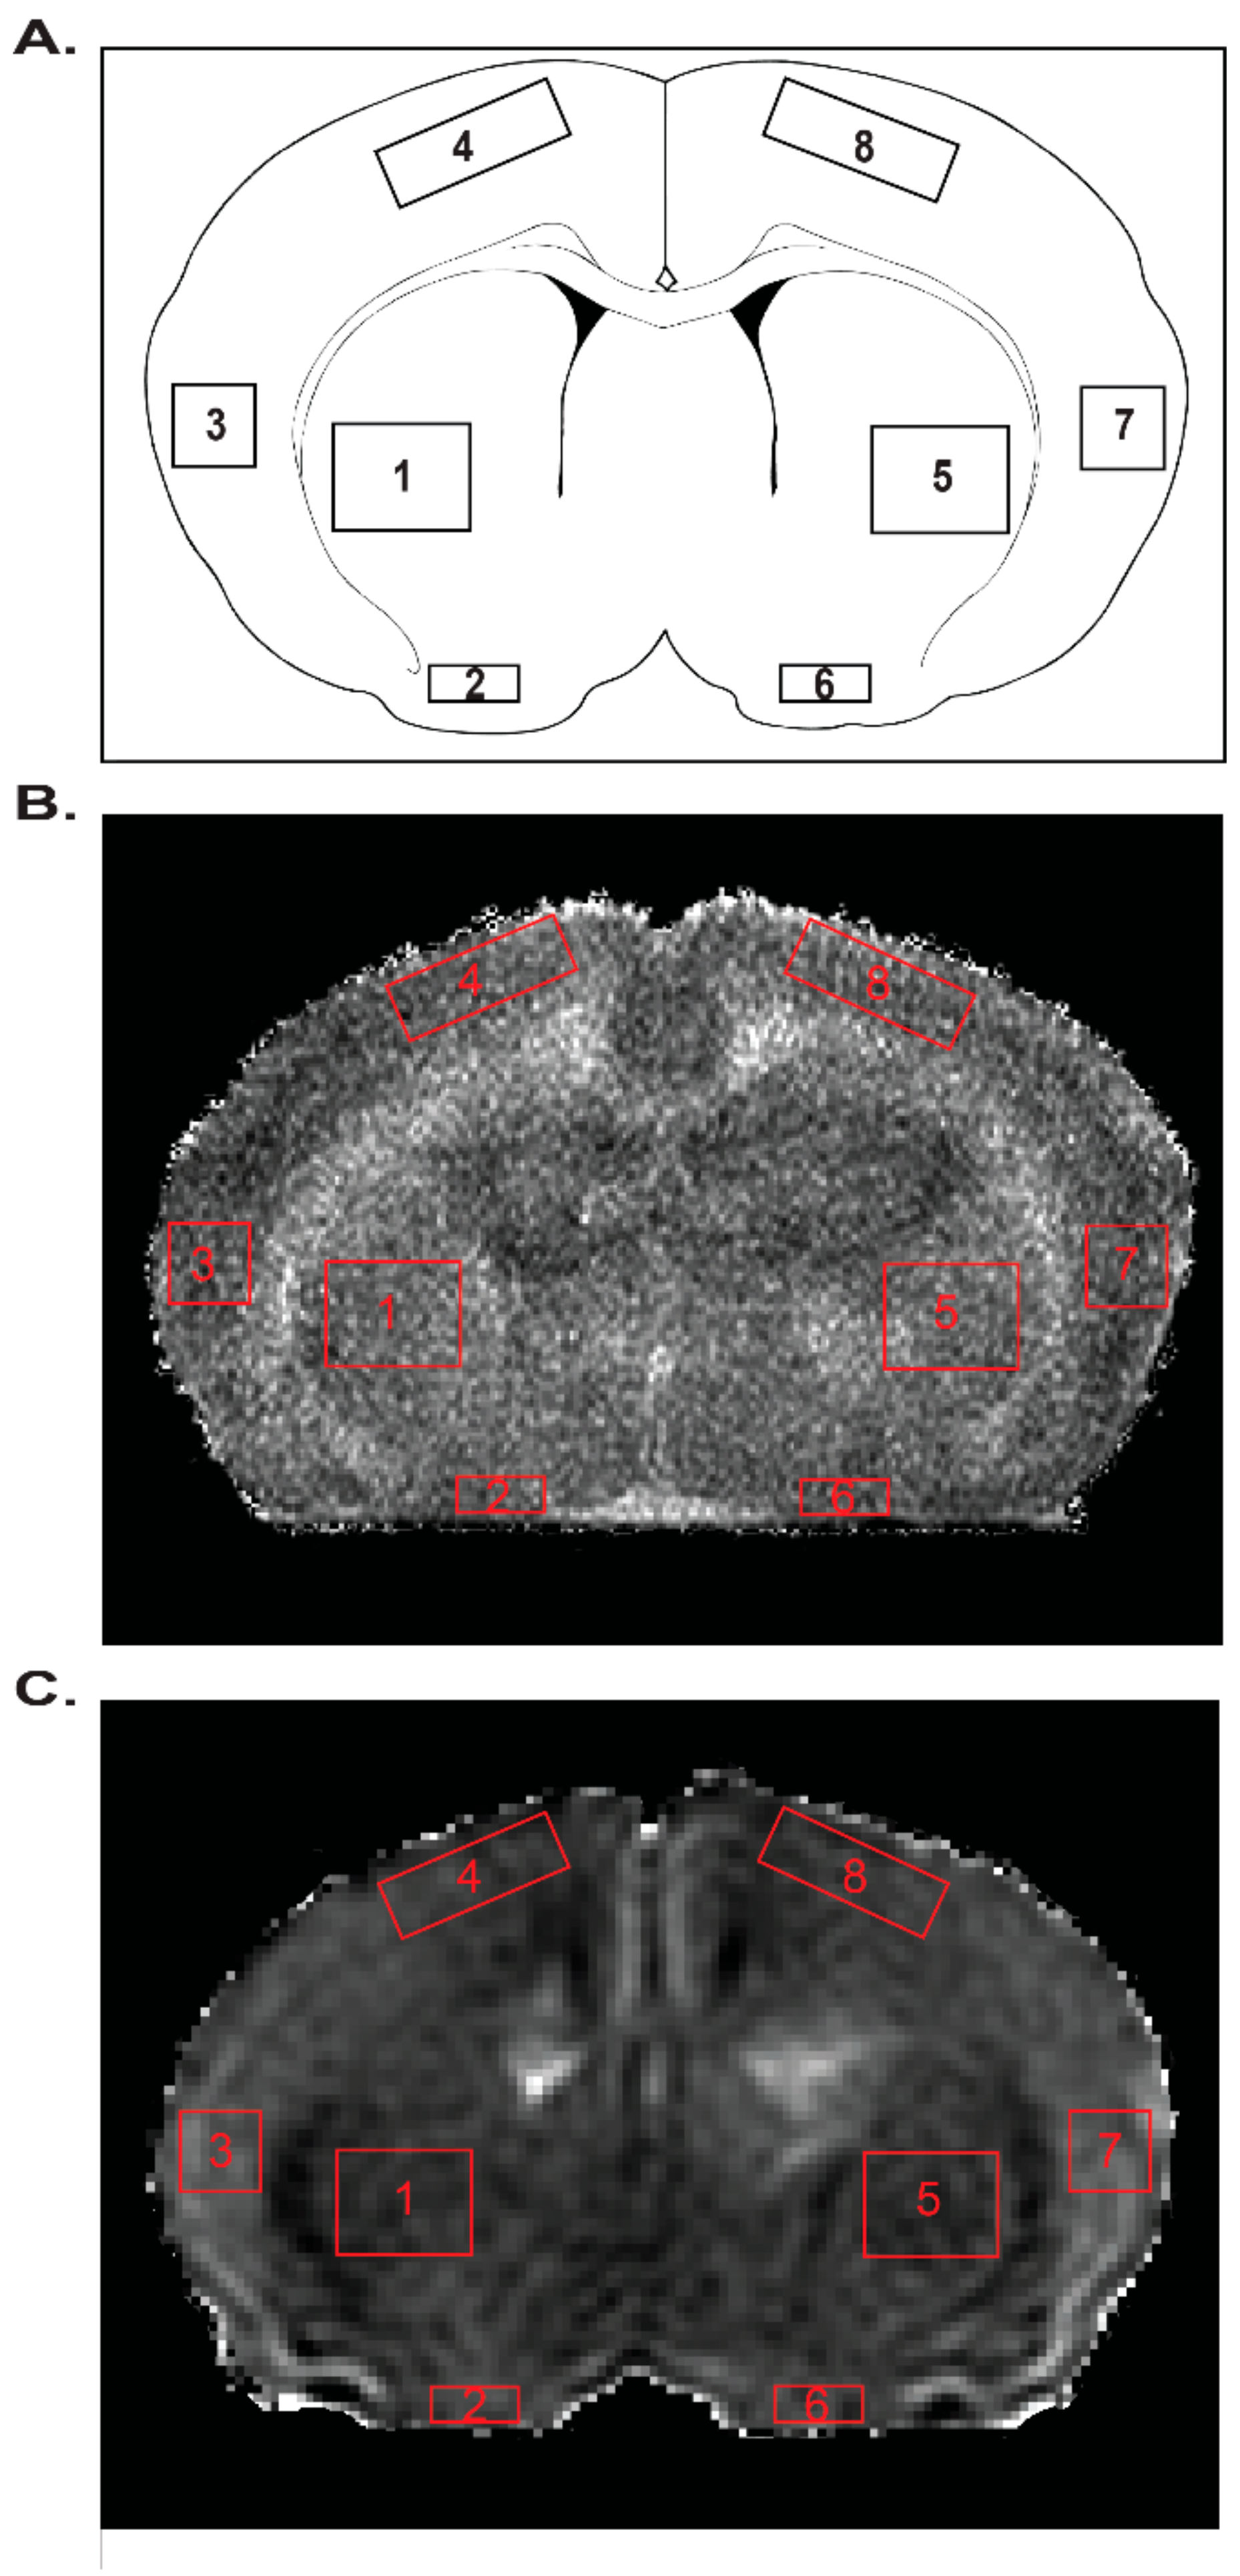

Analysis of T2 and ADC values portray the effects of mild neonatal HI, gestational MET transformation and MUN programming on neonatal cerebral tissue integrity four regions of interest in each hemisphere (Figure 7, Figure 8 and Figure 9). The methods used to measure these results could detect a difference of 3.3% (T2) and 6.2% (ADC) with a power of ≥0.8 for the number of pups used (n = 47). For comparisons between MUN groups, T2 values, which generally identify cerebral edema, did not significantly differ between any group (Figure 8A), confirming the very mild nature of the HI.

Figure 7.

(A) displays the location of each of the four regions of interest in each hemisphere, as marked by numbered red boxes on a coronal section from an anatomical map at Bregma level 0.20 mm. Regions of interest 1–4 represent the left striatum, ventral cortex, lateral cortex, and dorsal cortex, respectively, whereas regions of interest 5–8 represent the right striatum, ventral cortex, lateral cortex, and dorsal cortex, respectively. (B) shows a T2 map and (C) an ADC map from the brain of a P11 MUN Untreated-Sham rat.

An 11.7 T Bruker Avance instrument (Bruker Biospin, Billerica, MA, USA) generated images from ex vivo whole perfusion-fixed brains. As indicated by a growing number of studies, ex vivo MRI is highly useful for revealing changes in brain structure and water mobility [88]. Two imaging sequences (T2-weighted (T2WI) and diffusion weighted imaging (DWI)) assessed HI injury for changes in water content and water mobility, respectively. Each sequence collected 20 coronal slices with a slice thickness of 0.75 mm. The T2 sequence used the following parameters: TR/TE = 3000/10 ms, matrix = 192 × 192 zero-filled to 256 × 256 at reconstruction, field of view (FOV) = 1.5 cm, and a total of 2 averages. The DWI sequence employed these parameters: TR/TE = 5000/31.2 ms, b value = 200 s/mm2, matrix = 64 × 64 zero-filled to 128 × 128 at reconstruction, FOV = 1.5 cm, and a total of 2 averages. JIM, a medical imaging analysis software (Xinapse Systems Ltd.; West Bergholt, Essex, United Kingdom) generated T2 maps and processed the DWIs to produce ADC maps. Manually drawn regions of interest using FIJI sampled quantitative values in right (ipsilateral), left (contralateral to the side of carotid ligation), cortical, and striatal hemispheres for each slice of all ADC and T2 maps (Figure 7). For comparisons across groups, posterior/anterior analyses utilized the regional averages from the 13th or 14th coronal slice per animal for each group, starting from where the hippocampal formation is prominent (Bregma level 0.20 mm).